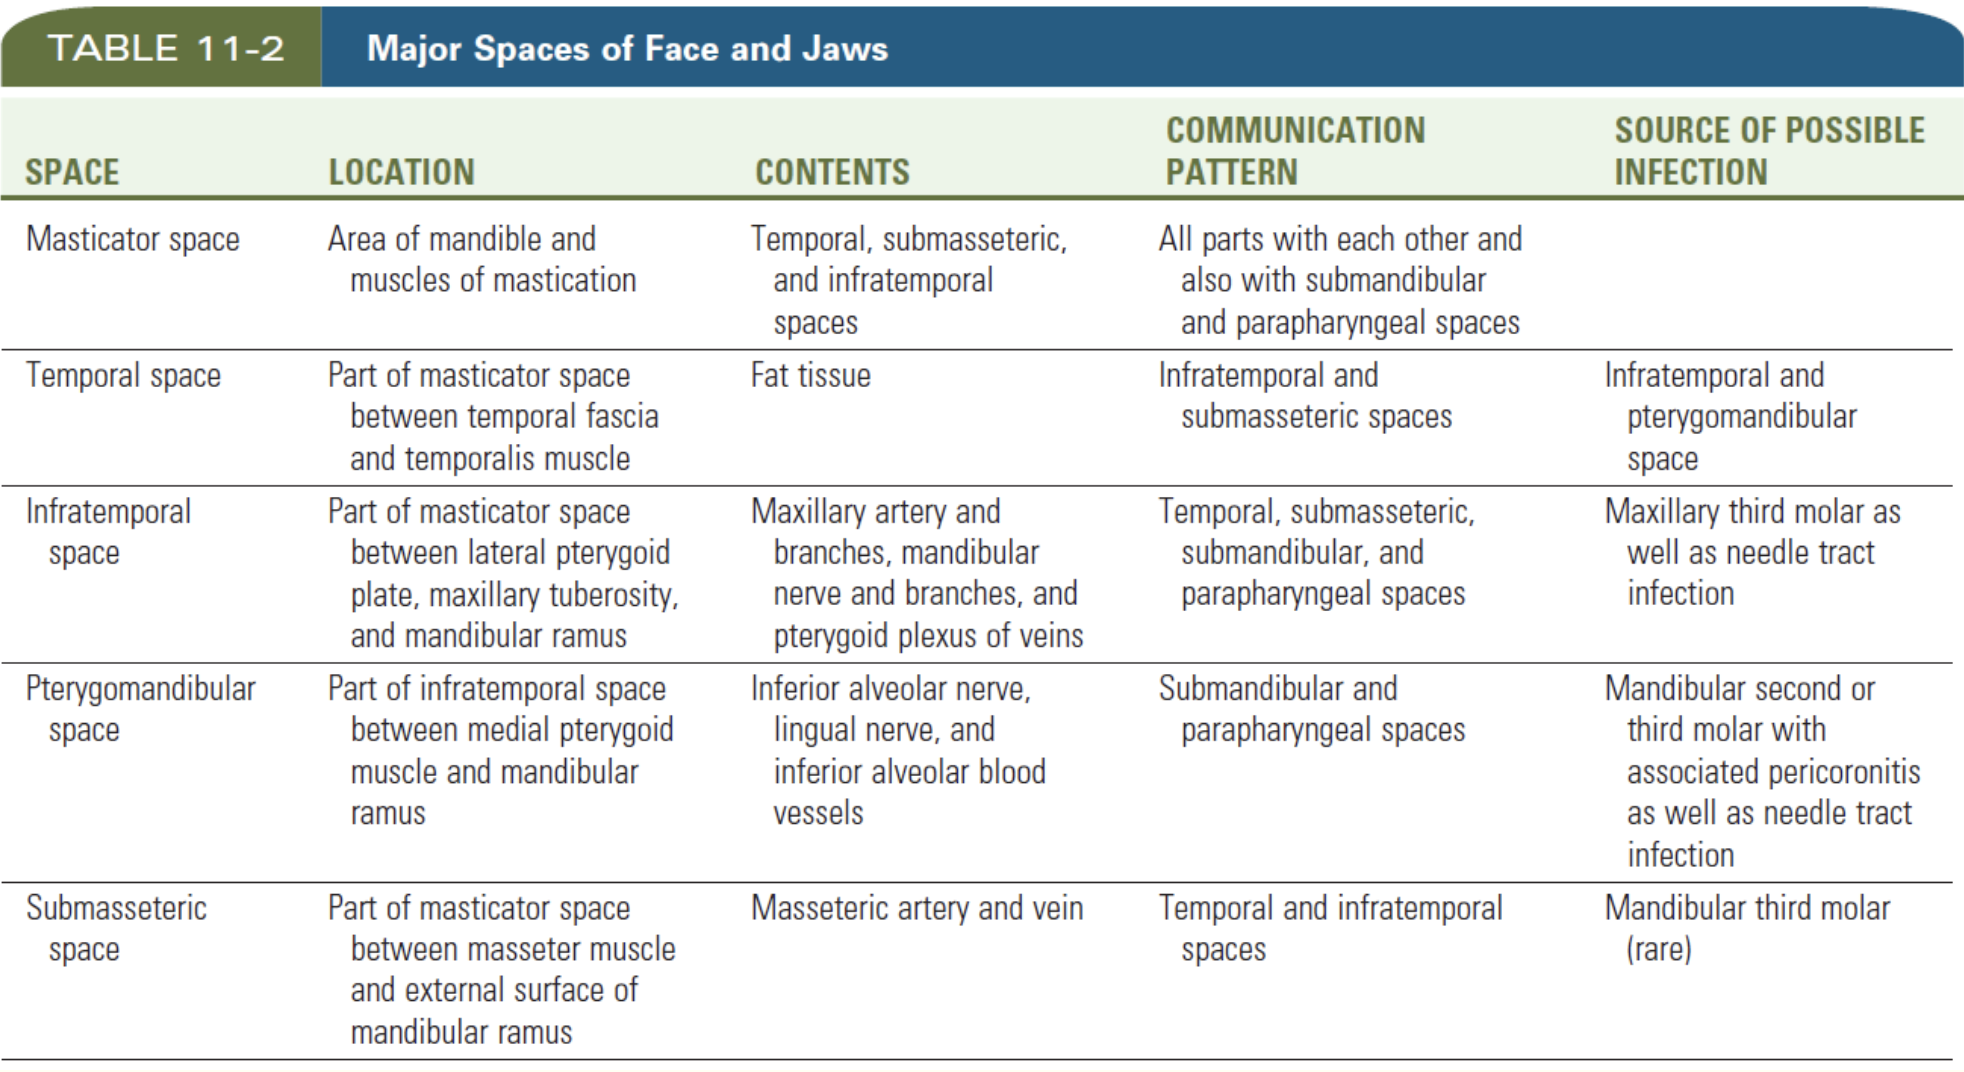

Space

Vestibular space

- of Maxilla

- of Mandible

Canine space (Maxilla)

- Nasolabial sulcus

Buccal space

- Buccal fat pad

- Parotid duct

- Facial a.

Parotid space

- Parotid g.

- Facial n.

- ECA

- Retromandibular v.

Masticator space

Temporal space

Temporalis m.分隔

- Superficial temporal space

- Deep temporal space

Infratemporal space

Zygomatic arch 以下

- 外側

- Temporalis

- 內側

- Pterygoid plate

- Maxillary a.

Pterygomandibular space

Med. pterygoid m.外

- Inf. alveolar a./ v./ n.

- Lingual n.

Submassetric space

Submental & Submandibular space

Submental

- Digastric, Hyoid bone, Mandibular symphysis 為界

- Superficial cervical fascia為底,Mylohyoid m. 為頂

Sublingual space

- Lingual n./a.

- Hypoglossal n.